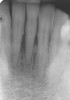

A 53-year-old male presented with localized advanced periodontal disease of the mandibular incisors. Teeth Nos. 23 to 26 exhibited Class II mobility because of advanced bone loss (Figure 1). The teeth had migrated out of position over the years, and a diastema had developed between No. 24 and No. 25 (Figure 2). The patient complained about the poor esthetic appearance of these teeth, and he was able to perceive their loss of strength on function as a result of their mobility.

Radiographic and clinical examination determined there was a sufficient volume of bone for implant placement. The facial walls of bone were intact. The patient was advised extractions and immediate placement of two implants with a nonocclusally loaded provisional restoration would be the treatment of choice. The patient understood at the time of extraction and implant placement that if the stability of one or both implants was not sufficient for immediate loading, he would have no choice but to accept a removable or bonded interim provisional restoration. He was informed that his postoperative instructions would include a diet of soft foods only for the first 6 to 8 weeks following surgery.

Preoperatively, 1 g of amoxicillin was administered. Using local anesthesia (lidocaine 1:100,000 epinephrine), extractions of teeth No. 23 to No. 26 were performed without raising a flap and with gentle luxation to preserve the remaining facial osseous plate. The sockets were curetted prior to implant placement. A vacuum-formed surgical guide, fabricated based on a diagnostic wax-up of the desired tooth positions for the subsequent fixed prosthesis, was used during implant placement. Osteotomies were performed at sites No. 23 and No. 26 and positioned toward the lingual aspects of the sockets (Figure 3A and Figure 3B). Two tapered implants (OsseoTite™ 313, BIOMET 3i™, Palm Beach Gardens, FL) measuring 3.25 mm x 13 mm were placed. Conical prosthetic abutments (3-mm height) were used to facilitate joining the two implants in a screw-retained fixed partial denture (Figure 4). A laboratory-processed acrylic-resin provisional restoration was altered to allow connection to the temporary cylinders. The provisional was placed into the vacuum-formed surgical guide that was now used to maintain the provisional in the correct 3-dimensional position (Figure 5) while being attached to the temporary cylinders with acrylic resin intraorally. Once a sufficient amount of acrylic resin was placed to secure the cylinders to the provisional, it was removed from the mouth and its contours were completed at the laboratory bench (Figure 6A). The two central incisor sockets were grafted with small-particle allograft material (Puros® Allograft, Zimmer Dental, Carlsbad, CA) to maintain gingival architecture beneath two ovate pontics (Figure 6B). The provisional restoration was inserted and the screws tightened to 20 Nt-cm of torque.